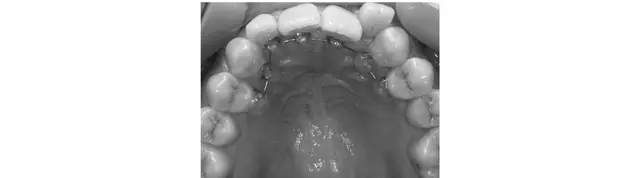

マウスピース矯正

取りはずしができるので食事や歯磨きにストレスなし

固めのマウスピースを長時間装着し歯並びを整える方法。部分にも対応し、矯正後の後戻りの調整にも最適。透明で目立ちにくく、取りはずし可能なので、食事や歯磨きがしやすい。ただし一日の装着時間が短いと矯正期間が延びる。目安は上下で¥480,000〜。